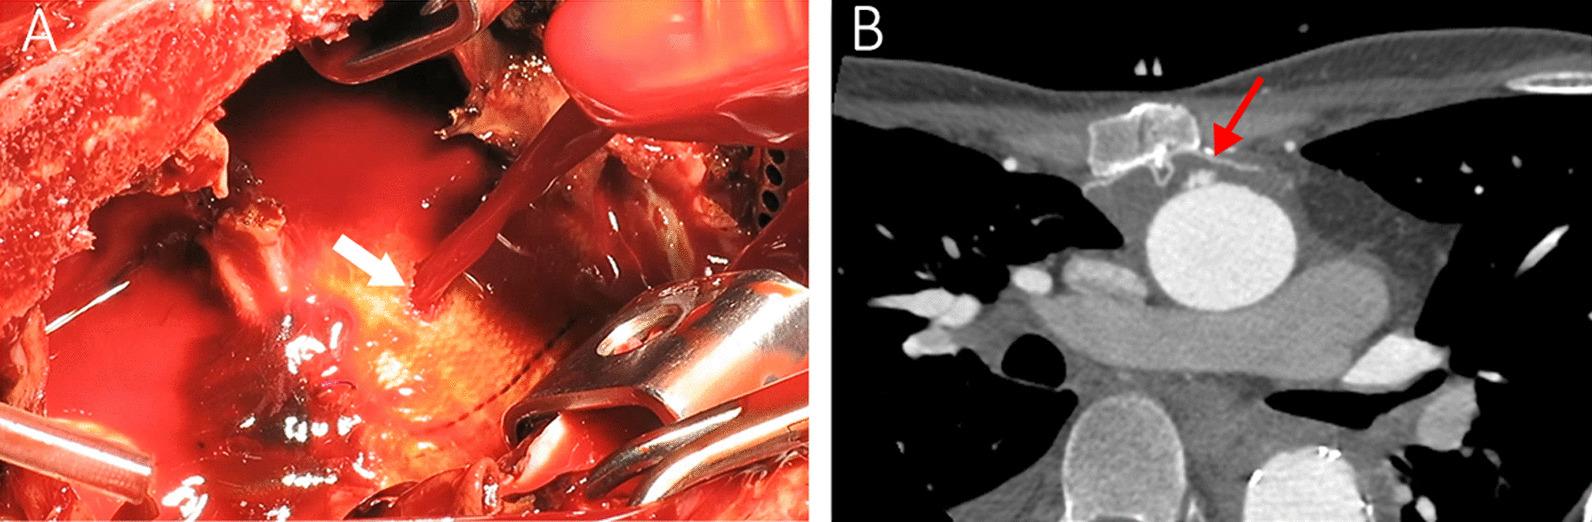

A 34-year-old man, known case of Marfan syndrome, with history of two prior aortic surgeries for aneurysm of ascending aorta, arch and thoracoabdominal aorta, presented with hemoptysis. The hemoptysis originated from an aortobronchial fistula secondary to a huge ascending aorta Dacron graft pseudoaneurysm. The graft erosion and subsequent pseudoaneurysm was caused by a fractured sternal wire. Surgical repair of the pseudoaneurysm was performed successfully and a Gore-tex patch was placed behind the sternum over the graft to prevent further direct contact of the wire and the graft.

一名 34 岁男性,患有马凡综合征,曾因升主动脉、弓部和胸腹主动脉动脉瘤进行过两次主动脉手术,因咯血就诊。咯血源于升主动脉涤纶移植物巨大假性动脉瘤引起的支气管-主动脉瘘。移植物侵蚀和随后的假性动脉瘤是由胸骨钢丝断裂引起的。成功地对假性动脉瘤进行了手术修复,并在胸骨后面的移植物上放置了 Gore-tex 补丁,以防止钢丝和移植物进一步直接接触。